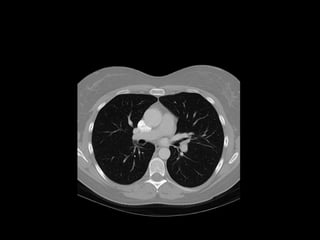

The document discusses the anatomy of the chest x-ray and CT scan by describing the lobes of the lungs and their locations. It also mentions the heart, mediastinum, hilum, and ribs. Several axial, coronal, and sagittal CT images are included with labels pointing out structures like the trachea, bronchi, lobes of the lungs, and fissures. In summary, the document provides an overview of lung and chest anatomy as seen on x-rays and CT scans through text descriptions and labeled medical images.